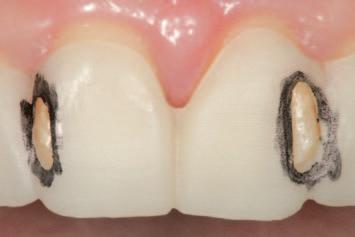

n Tooth structure is reduced until it conforms precisely to the contours of the preparation guide. The removal of the contrasting marker ink, caused by direct contact with the rotating diamond bur, indicates that the target reduction depth has been achieved. This visual endpoint ensures accurate, conservative preparation aligned with the contours of the planned definitive

(

restoration

Figure 4).

FIGURE 4: The appearance of the guide following the tooth reduction procedure. The clinician should stop the procedure the moment the contrasting ink has been displaced.

A C B

FIGURE 5: Evaluation of the clinical situation before and after the planned tooth reduction, highlighting the subtle and conservative but clinically meaningful changes that have been made, prior to tooth preparations for indirect restorations.

n Upon removal of the tooth reduction guide, a subtle, conservative but clinically meaningful elimination of anticipated interferences may be confirmed (Figure 5). The guided reduction procedure has simplified the subsequent process of tooth preparation for indirect restorations, at the next step of the treatment plan.